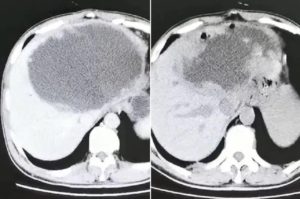

ଏକ ରିପୋର୍ଟ ଅନୁଯାୟୀ, ଚାଇନାର ହାଙ୍ଗଝୁରେ ରହୁଥିବା ୫୫ ବର୍ଷୀୟ ଜଣେ ବ୍ୟକ୍ତିଙ୍କୁ ଅଧା ରନ୍ଧା ମାଛ ତରକାରୀ ଖାଇବା ମହଙ୍ଗା ପଡ଼ିଛି। ପେଟରେ ଦରଜ ହେବା, ବାନ୍ତିହେବା, ଥକ୍କା ଲାଗିବା ଏବଂ ଭୋକ ନ ହେବା ପରି ଲକ୍ଷଣ ତାଙ୍କଠାରେ ଦେଖାଦେଇଥିଲା। ଏସବୁ ସମସ୍ୟା ଭୋଗିବା ପରେ ଡାକ୍ତରଙ୍କ ନିକଟକୁ ଯାଇଥିଲେ। ୪ ମାସ ଧରି ଔଷଧ ଖାଇବା ପରେ ମଧ୍ୟ କମି ନ ଥିଲା। ଡାକ୍ତରଙ୍କ ନିକଟକୁ ପୁଣି ଥରେ ଯିବାରୁ ଡାକ୍ତର ସ୍କାନ୍ କରିବାକୁ ପରାମର୍ଶ ଦେଇଥିଲେ। ସ୍କାନ୍ରେ ଡାକ୍ତର ଯାହା ଦେଖିଲେ ଆଶ୍ଚର୍ଯ୍ୟ ହୋଇଗଲେ। ଏହି ବ୍ୟକ୍ତିଙ୍କୁ କ୍ଲୋନୋକାୟାସିସ୍ ନାମକ ଇନ୍ଫେକ୍ସନ ହୋଇଥିଲା। ଯାହାର କାରଣ ପାରାସାଇଟ୍ ( ଏକ ପ୍ରକାର ପୋକ)। ଯାହାକୁ ଫ୍ଲାଟ୍ଓ୍ବର୍ମ କୁହନ୍ତି। ଏହି ଓ୍ବର୍ମ ବା କୃମି ପେଟ ଭିତରକୁ ଚାଲିଯାଇଥିଲା। ବ୍ୟକ୍ତିଙ୍କ ଲିଭର ବା ଯକୃତରେ ଅଣ୍ଡା ଦେବା ଆରମ୍ଭ କରିଥିଲା। ପେଟ ଭିତରେ ଏକ ବଡ଼ ଥଳି ବଢ଼ିବାକୁ ଲାଗିଥିଲା।

ଡାକ୍ତରଙ୍କ ଅନୁଯାୟୀ, ଏହି କୃମି ଯେଉଁ ଥଳିରେ ବଢ଼ିଥିଲା, ତାହା ୧୯ ସେଣ୍ଟିମିଟର ଲମ୍ବ ଏବଂ ୧୮ ସେଣ୍ଟିମିଟର ଚଉଡ଼ା ଏବଂ ୧୨ ସେଣ୍ଟିମିଟର ଥିଲା। ଏହି କାରଣ ଯୋଗୁ ଲିଭରରେ ମଧ୍ୟ ଛୋଟ ଛୋଟ ଟ୍ୟୁମର ହୋଇଥିଲା। ତେବେ ଲିଭର ଅପରେଶନ କରିବା ପାଇଁ ଡାକ୍ତର ନିଷ୍ପତ୍ତି ନେଇଥିଲେ। ସେଥିରୁ ଅସଂଖ୍ୟ ଛୋଟଛୋଟ ଅଣ୍ଡା ପାଇଥିଲେ। ଏହି ବ୍ୟକ୍ତିଜଣକ ଏବେ ହସ୍ପିଟାଲରେ ଅଛନ୍ତି। ତାଙ୍କ ସ୍ବାସ୍ଥ୍ୟାବସ୍ଥା ଗୁରୁତର ଥିବା ଡାକ୍ତର କହିଛନ୍ତି।